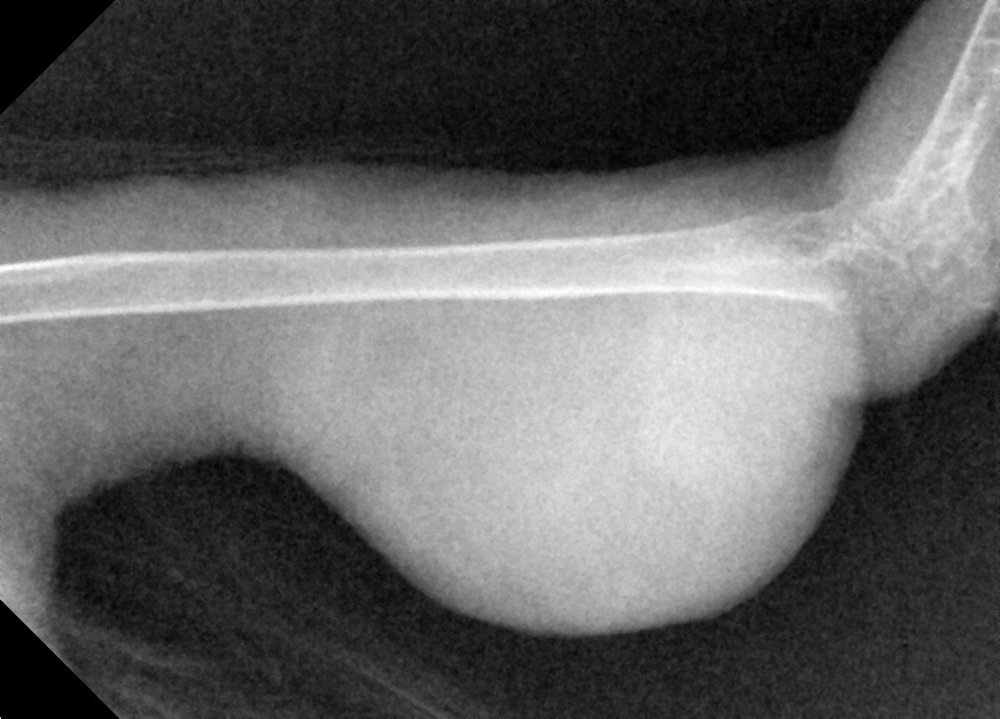

Zosia Опубликовано 30 января, 2020 #16 Опубликовано 30 января, 2020 Кость целая,без патологических изменений, без зон распада или абсцессов Броди. Возможно есть какие-то проблемы в суставе (кажется низковатой плотность, возможно след старой травмы СУСТАВА). Я сделала инверсию снимка, видится некое образование,кистоподобное, на латеральной проекции. Возможно исходит из суставной сумки (цифра 1). Это м.б. абсцессом, гигромой- но связано скорее всего с соедигнительной тканью. На склеродермию или подагрическое образование непохоже. На ВД проекции в нижней четверти кости есть (возможно это артефакт) некое нарушение четкой границы кости (цифра 2)... но параметры снимка не позволяют с уверенностью эту неровность оценить. Вопросы: Есть ли проблемы с дыханием Есть ли проблемы с пищеварением (рвота напрмиер) И нужен рентген "всей птицы", хотя бы один...

Dukemc Опубликовано 31 января, 2020 Автор #26 Опубликовано 31 января, 2020 23 часа назад, Zosia сказал: Кость целая,без патологических изменений, без зон распада или абсцессов Броди. Возможно есть какие-то проблемы в суставе (кажется низковатой плотность, возможно след старой травмы СУСТАВА). Я сделала инверсию снимка, видится некое образование,кистоподобное, на латеральной проекции. Возможно исходит из суставной сумки (цифра 1). Это м.б. абсцессом, гигромой- но связано скорее всего с соедигнительной тканью. На склеродермию или подагрическое образование непохоже. На ВД проекции в нижней четверти кости есть (возможно это артефакт) некое нарушение четкой границы кости (цифра 2)... но параметры снимка не позволяют с уверенностью эту неровность оценить. Вопросы: Есть ли проблемы с дыханием Есть ли проблемы с пищеварением (рвота напрмиер) И нужен рентген "всей птицы", хотя бы один...

Zosia Опубликовано 1 февраля, 2020 #27 Опубликовано 1 февраля, 2020 На второй лапе- зона артроза или подагрических отложений (четкости никакой).